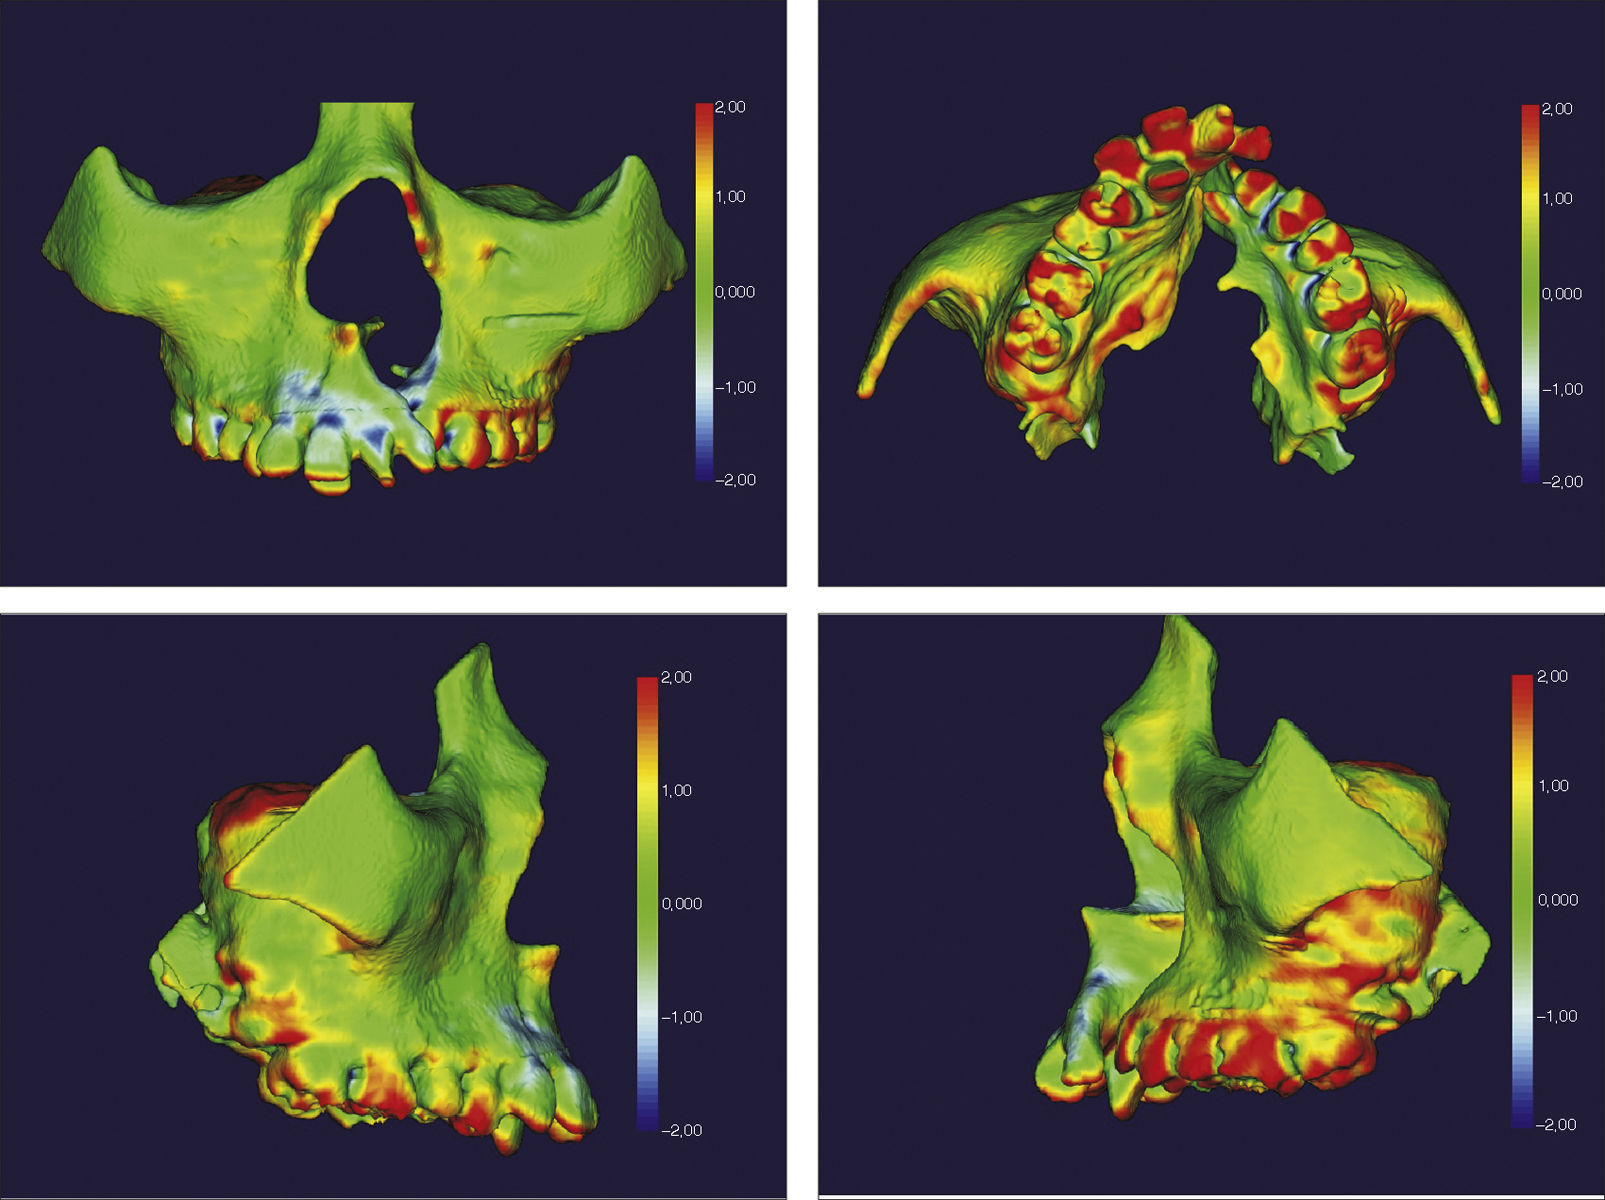

O surgimento e o aumento da acessibilidade da TCFC agregaram uma maior credibilidade ao diagnóstico clínico e às investigações científicas no estudo das deformidades craniofaciais19. Todavia, as informações 3D fornecidas pelas TCFC ainda vêm sendo rotineiramente analisadas de forma 2D, por medidas lineares em cortes ortogonais5,20. A construção e sobreposição de modelos virtuais 3D ainda é uma metodologia pouco difundida. Este estudo é um dos pioneiros que utiliza este método para avaliação de ERM em pacientes com fenda. A sobreposição baseia‐se na construção dos modelos virtuais 3D, utilizando o software SLICER21, pelos arquivos obtidos na TCFC, seguida pela sua justaposição, que utiliza a base do crânio como referência e a final obtenção dos métodos de medidas intitulados: sobreposição por semitransparência e mapa por códigos de cores22. A sobreposição por semitransparência revela uma análise qualitativa, em que o momento pós‐tratamento é retratado por uma malha preta translúcida, sobre o modelo inicial em vermelho (figs. 9 e 10). O aparelho em leque demonstrou um deslocamento de quase todos os dentes para vestibular e uma movimentação vestíbulo‐posterior do segmento menor (lado esquerdo [fig. 9]). O mapa por códigos de cores permite um complemento da análise visual, sendo que cada cor reflete uma alteração na posição das estruturas: azul – recuo; verde – estabilidade e vermelho – expansão. A intensidade da cor está diretamente relacionada à quantidade de movimentação. Todo o mapa é seguido por uma escala, com os valores em milímetros para cada cor (figs. 11 e 12). A observação feita na sobreposição por semitransparência do expansor em leque é confirmada no mapa por código de cores e nas medidas lineares. Uma menor porção de vermelho é visualizada em molares, quando comparada aos pré‐molares. O deslocamento para posterior e vestibular do menor segmento é constatado pela presença de azul na mesial dos dentes e vermelho nas eminências alveolares do lado em questão. Diferentes tonalidades de azul são vistas na cervical dos incisivos, possivelmente uma retroinclinação em decorrência da ausência de apoio mecânico no local. Para a quantificação das mudanças no posicionamento dentário, primeiramente identificou‐se, nos 3 cortes ortogonais, os pontos de referência para a medida (ponta da cúspide mésio vestibular dos primeiros molares superiores e ponta da cúspide dos caninos), tanto do lado direito como do lado esquerdo, utilizando o software ITK Snap23. Os pontos foram marcados com uma esfera de 0,5mm de diâmetro, identificando a posição 3D destas referências no espaço (fig. 13). A aferição das distâncias Euclidianas entre as esferas foi realizada com o auxílio da ferramenta Q3DC no programa SLICER23. O paciente A obteve um aumento de 3mm na distância intercanina e de 6mm na distância intermolar. Na elucidação do paciente que utilizou o disjuntor mini‐Hyrax invertido com BTP (B), observa‐se na sobreposição por semitransparência um deslocamento vestibular, principalmente dos pré‐molares e uma constância das demais áreas, achados corroborados no mapa por código de cores. A área que não está verde é a região de pré‐molares, vermelho por vestibular e azul por palatino, notando uma tonalidade entre verde e vermelho (amarelo) no corpo da maxila do lado menor (esquerdo). A oclusal dos molares, em vermelho, representa a erupção dos elementos.

Sobreposição com semitransparência dos modelos 3D do tratamento com o aparelho em leque. Antes da expansão representado por vermelho e após a expansão pela malha fina translúcida. Observa‐se um trespasse da malha preta para vestibular em molares, pré‐molares e canino, indicando que houve expansão em toda essa região.

Sobreposição com semitransparência dos modelos 3D do tratamento com o aparelho mini‐Hyrax invertido com BTP. Antes da expansão representado por vermelho e após a expansão pela malha fina translúcida. Observa‐se um trespasse da malha preta para vestibular na região dos pré‐molares, indicando expansão concentrada nessa região.